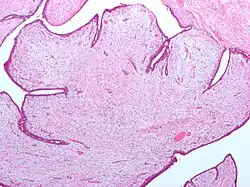

| Fibroepithelial neoplasm (Phyllodes tumor). | |

A fibroepithelial neoplasm (or tumor) is a biphasic tumor. They consist of epithelial tissue, and stromal or mesenchymal tissue. They may be benign or malignant.[1]